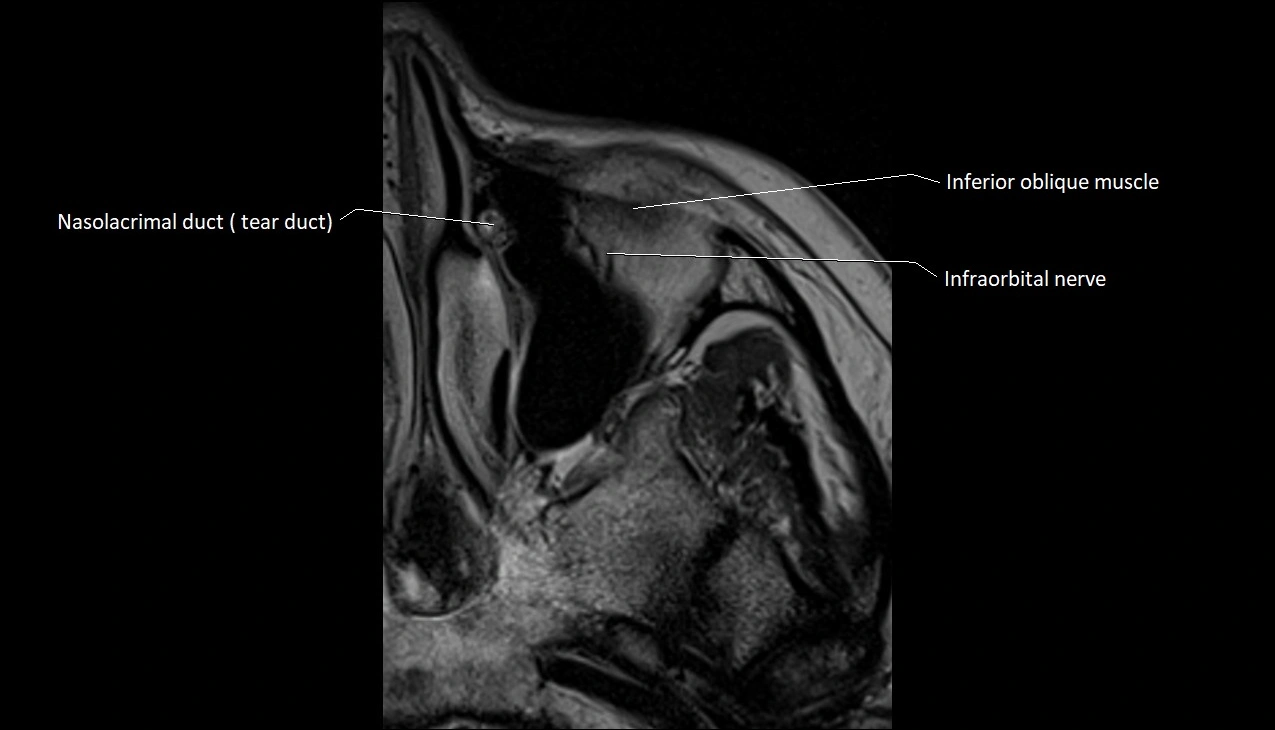

- Inferior oblique muscle

- Nasolacrimal duct (Tear duct)

- Infraorbital nerve